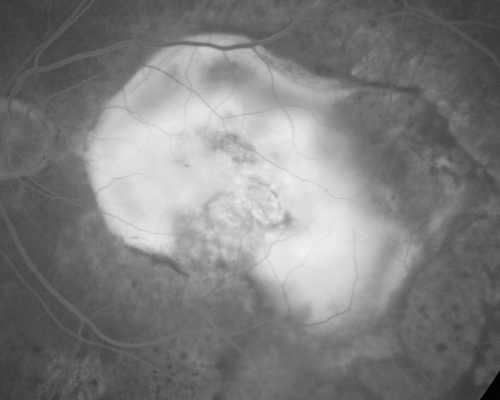

Macular Scar Left Eye from Age-Related Macular Degeneration

81-year-old woman has a macular scar in the left eye and then unfortunately developed a central retinal artery occlusion in the right eye OD 20/100, OS 6/200.